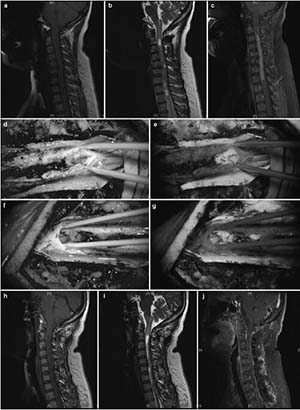

20171023161742 Figure 3 Intramedullary ependymomas at C3–C7, and tumor-associated stroke. (a) Preoperative T1 image showing spinal cord thickening and cysts in the septum. (b) Preoperative T2 image of a mass at C3–C7 and cysts in the septum. Stroke was not detected. (c) Preoperative enhanced magnetic resonance image showing an intramedullary tumor as a distinctive mass at C3–C7. Stroke enhancement was undetected. (d) Indistinct tumor images, intraoperatively, under fluorescent illumination. (e) Distinct intraoperative image of a tumor under the microscope. (f) Intraoperative and 1-month postoperative T1 images show the absence of tumor residuals or relapses. (g) T2 images, 1 month after surgery, show the absence of tumor residuals and relapses.